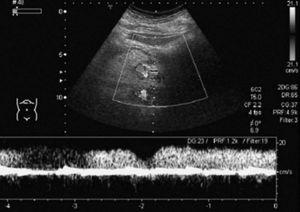

La TC helicoidal permitió, además, llevar a cabo un estudio detallado de los pequeños vasos arteriales y venosos peripancreáticos24-26 (fig. 2), mostrando mejores resultados que la angiografía por sustracción digital en el diagnóstico de la invasión vascular por cáncer de páncreas27. La valoración de estas pequeñas estructuras vasculares mejora el rendimiento de la TC en la estadificación tumoral28,29. La posibilidad de reconstruir en diferentes planos del espacio las imágenes axiales obtenidas ha sido evaluada por algunos autores30,31, obteniendo un mayor rendimiento de la TC para determinar la invasión vascular, fundamentalmente venosa, cuando las secciones transversas se interpretan en combinación con las reconstrucciones multiplanares que cuando se interpretan únicamente las secciones transversas (92-96% frente a 69-70%) (fig. 3).

Fig. 2.--Estudio de tomografía computarizada con contraste endovenoso en fase pancreatográfica en un paciente con neoplasia del cuerpo pancreático. Múltiples vasos mesentéricos dilatados secundarios a la infiltración venosa portomesentérica tumoral (flechas).